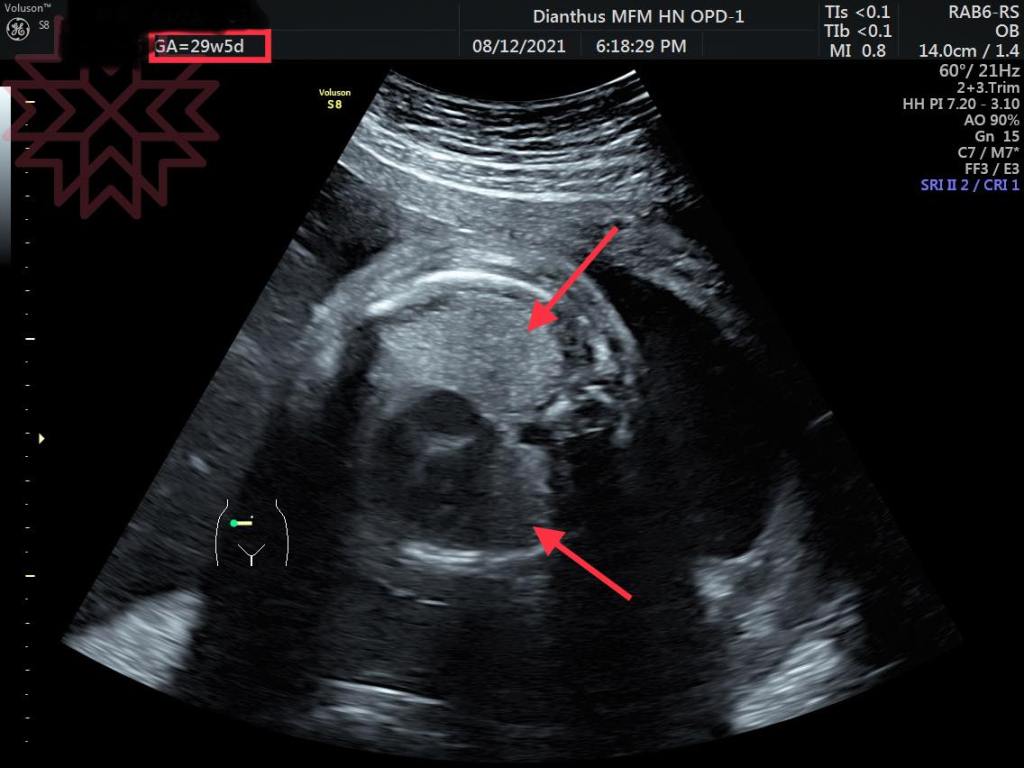

第三張是昨天29周時的照片

乳糜胸消失了

我們就是花兩個禮拜的時間想辦法把它變回正常